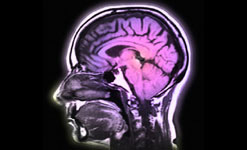

| Blood Brain barrier on Material World |

Blood Brain Barrier

The Blood Brain Barrier is an extraordinary mechanism.

Its been known about for well over 100 years but it’s only in the last 10 or 15 years that researchers have started to get an idea of the Blood Brain Barrier's role in diseases like MS, Alzheimer’s or Parkinson’s.

Quentin Cooper is joined by Professor Joan Abbott, Blood Brain Barrier group, King’s College, University of London and Professor Sanjay Sisodiya, Institute of Neuroscience, University College, University of London to find out more.